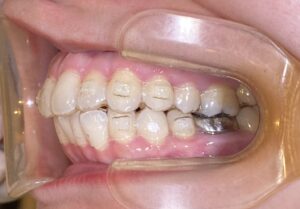

歯列矯正の治療が完了した後も、その後のケアが非常に重要です。理想的な歯並びを維持するためには、矯正治療後の適切なメンテナンスが必要不可欠です。今回は、矯正治療後のケアについて詳しくご紹介します。

矯正治療を終えた後、歯が元の位置に戻らないようにするためには「リテーナー」を使用します。リテーナーは、矯正治療が終わった後に歯を安定させるための装置で、治療後の歯並びを守るためには欠かせないアイテムです。

最初の数ヶ月は、リテーナーを毎日装着することが推奨されます。その後、歯並びが安定してきた段階で、使用頻度を減らしていきますが、歯科医師の指示に従い、適切に使い続けることが大切です。リテーナーをサボると、歯が元の位置に戻る可能性があるため、定期的に使用することが最も重要です。